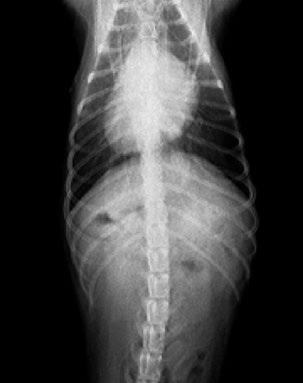

Issuu converts static files into: digital portfolios, online yearbooks, online catalogs, digital photo albums and more. Sign up and create your flipbook.